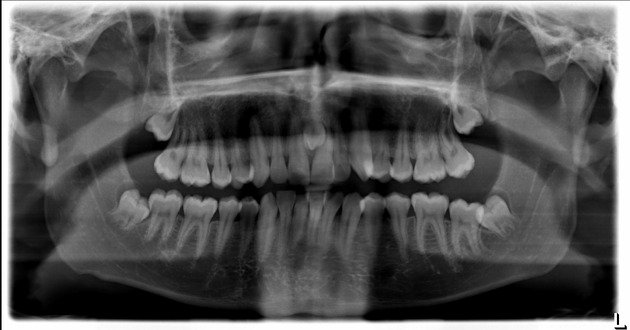

Radiographie Panoramique

La panoramique est l’examen de débrouillage incontournable. Elle permet d’évaluer :

- La position dans le plan vertical (hauteur d’inclusion)

- L’axe général de la dent

- Les rapports avec les dents voisines (résorptions ?)

- La présence d’odontomes ou de germes surnuméraires

Limite importante : la position vestibulaire ou palatine ne peut pas être formellement déterminée sur cet examen seul.